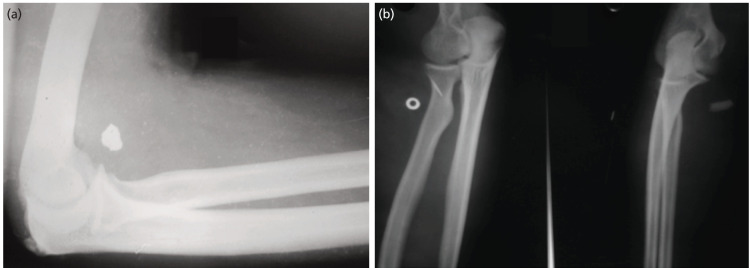

Materials and methods: This presentation is on a series of 18 cases of nerve injuries among industrial workers located from finger level up to the arm excluding the brachial plexus due to metallic foreign bodies entering while operating lathe machines over a period of two years with patients being followed-up over a one year period.

Results: Mean age in this series was 31.3 years with age range 16-40 years and all were males. Two patients had more than one nerve involvement and one patient had associated vascular injury. All the patients showed functional improvement. Most common nerve injured was median nerve. Most common site for nerve injury was forearm. Combined lesions most commonly involved the ulnar and median nerves.